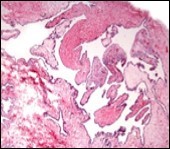

Figure 5.Cutaneous ciliated cyst with incomplete intervening septa and a lining of attenuated, ciliated epithelium along with supporting fibrous tissue (13).

Morphological analysis preponderantly demonstrates a solitary, uni-locular or multi-locular cyst of Mullerian origin with an epithelial lining recapitulating the epithelium of fallopian tube.

Cutaneous ciliated cyst is layered with a singular layer of ciliated epithelial cells which are chiefly constituted by cuboidal to columnar epithelium, traversed by partially configured fibrous tissue septa with an admixture of randomly dispersed, intraluminal papillary projections akin to those cogitated in the fallopian tube. Superimposed epithelium is inundated with well vascularized, parallel bundles of collagen although smooth muscle is absent 7, 8.